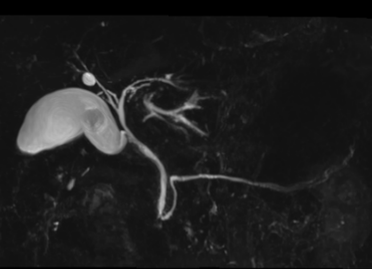

当院では、膵臓がんの早期発見・早期治療に繋げるべく、消化器病専門医による高精度3テスラMRIを活用した『MRI膵臓がんドック』を実施しております。

① MRIによる胆管膵管画像検査(MRCP) ② 血中腫瘍マーカー測定CEA・CA19-9・DUPAN-2) ※消化器病専門医による結果説明あり |